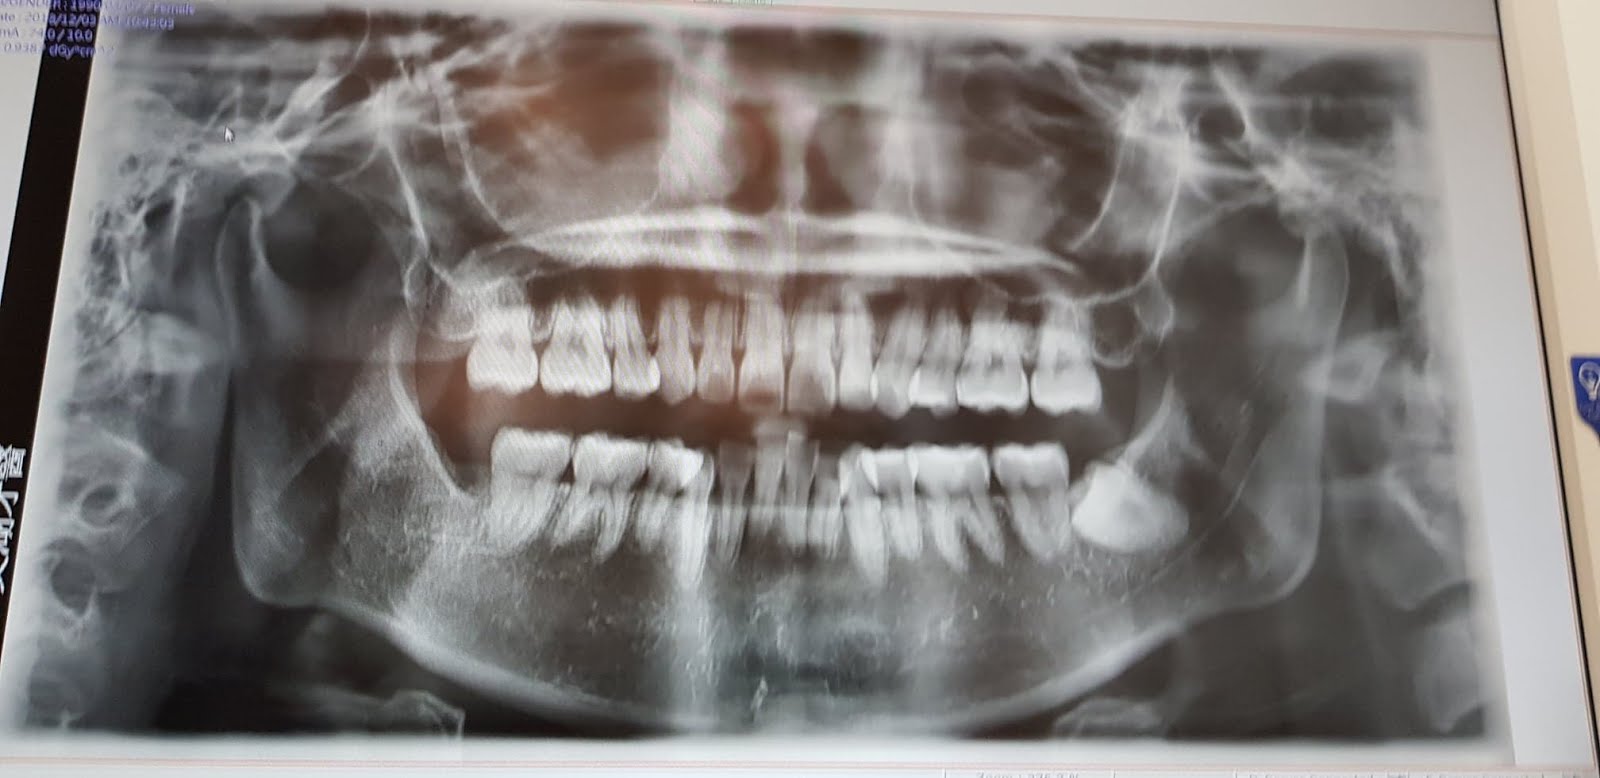

因為要拔的牙是躺著的智齒

於是我去找了智齒之神醫歐嘉得(一家只專門拔智齒的牙醫診所)